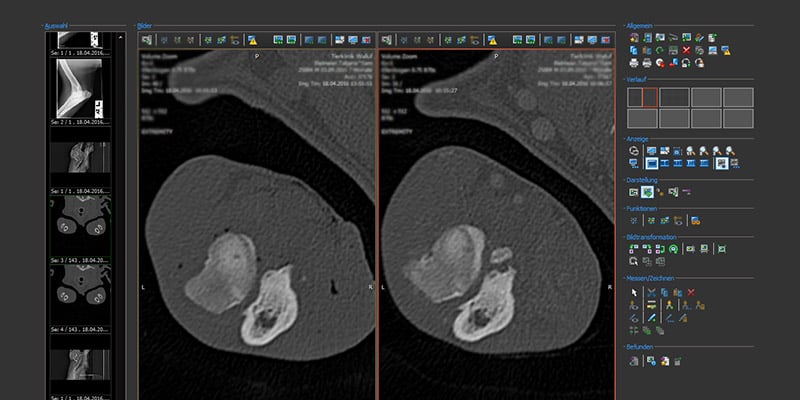

Computertomographie:

Wir raten in der Regel zur CT - Diagnostik und Arthroskopie der Ellbogen, um einen möglichst genauen Befund zu erhalten.

Zur CT - Untersuchung ist eine leichte Narkose notwendig, um keine Bewegungsartefakte zu generieren. Es ist eine sehr sensitive Untersuchung, um schon frühe Veränderungen des Coronoid zu erkennen und zur Messung einer Ellbogeninkongruenz.

Das CT gibt uns äußerst wichtige Informationen, um eine bestmögliche Behandlungsplanung bei Ihrem Hund vorzunehmen. Daher empfehlen wir eine CT - Untersuchung des Ellbogens auch bei jedem Hund mit Verdacht auf ED. Dabei können wir binnen weniger Minuten einen detaillierten dreidimensionalen Blick in jedes Gelenk werfen.